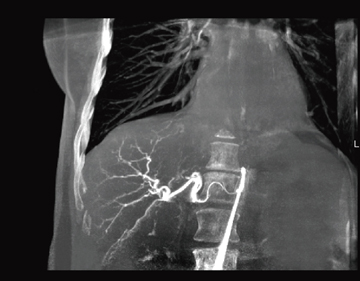

2.syngo Embolization Guidance

iGuideと同様に,TAEの手技を迅速に支援するツールが,“syngo Embolization Guidance”である。術中に撮影されたDynaCT画像から,血管塞栓術で重要となる腫瘍血管の位置を容易に判別し,術中のマイクロカテーテルを速やかに目的血管まで誘導する(図6)。明確な目的血管の同定は,治療時間の短縮につながり,被検者負担の大きな要因となる被ばくと使用造影剤量の低減を手助けする。

図6 HCCへの支配血管の識別(画像提供:Siemens AG)